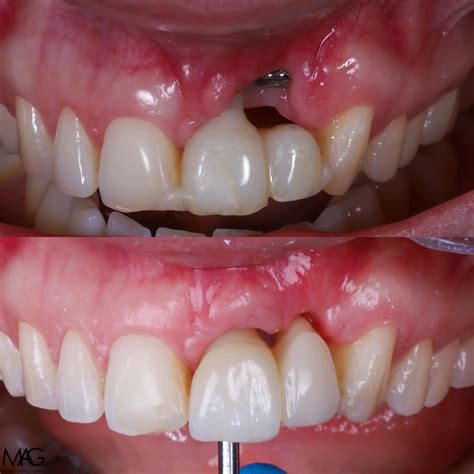

Además, los implantes cigomáticos son una excelente alternativa en casos de pérdida ósea severa en el maxilar superior. Estos implantes se anclan en el hueso cigomático (pómulo), evitando la necesidad de un injerto óseo en el maxilar. Al contrario que los implantes osteointegrados convencionales, que se colocan encima del maxilar, los cigomáticos se insertan en diagonal, en el arco de las mejillas.

Testimonios de Pacientes

Conoce los testimonios de pacientes reales de clínicas odontológicas que se han realizado un tratamiento de implantes dentales con elevación de seno maxilar e injerto dental:

- “El doctor Ferrer es dueño de mi sonrisa. El trato ha sido siempre maravilloso y los precios los mejores de Madrid. Me han puesto varios implantes y el resultado es super natural."